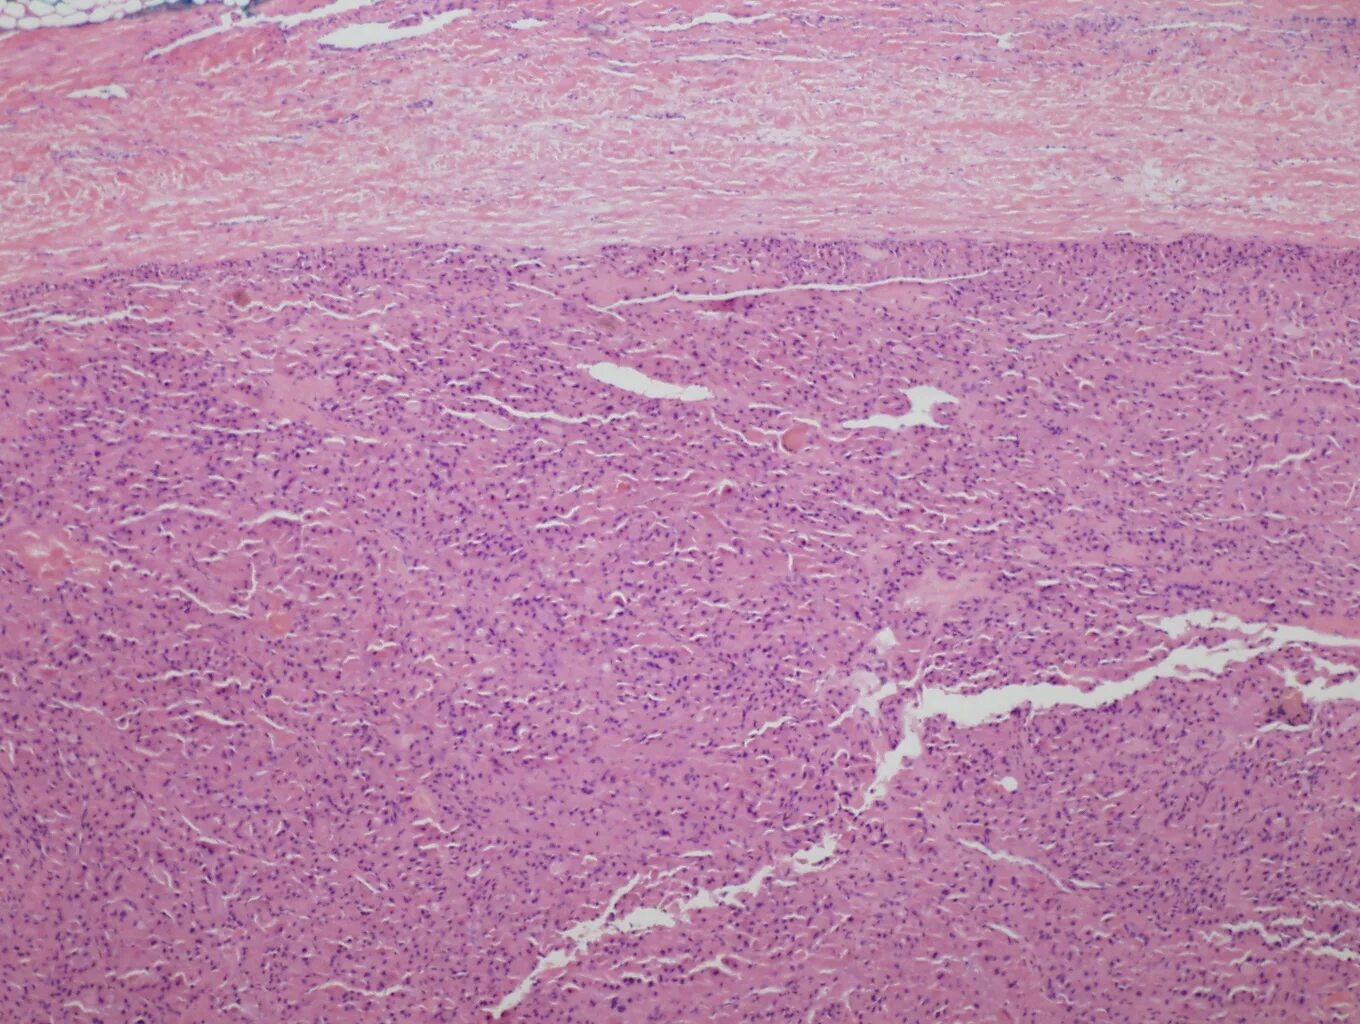

Гистология фото